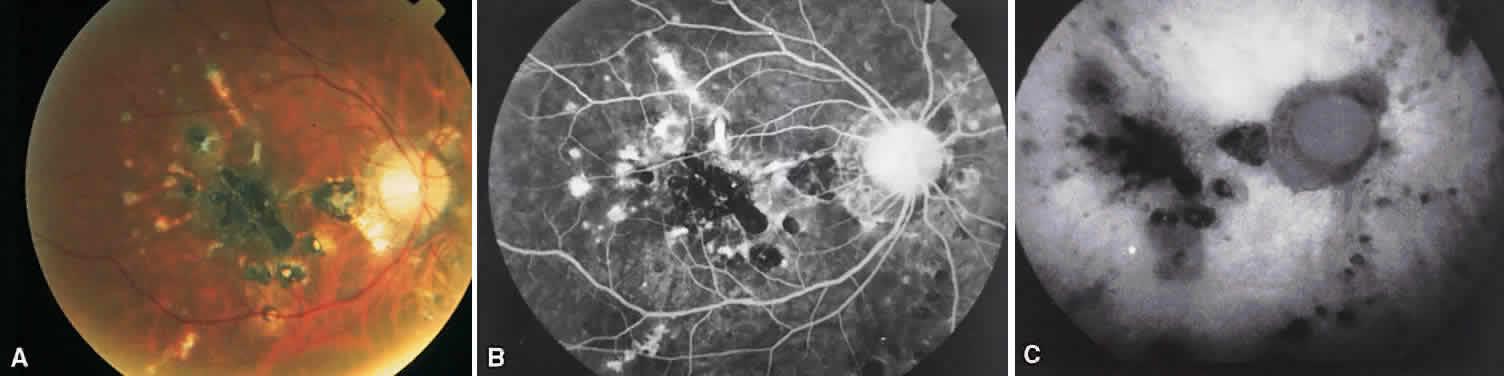

MULTIFOCAL CHOROIDITIS

Multifocal choroiditis may mimic the typical clinical findings of presumed ocular histoplasmosis syndrome (discussed later) and has the additional finding of anterior chamber and vitreous cells. Multiple yellow or gray acute choroidal lesions measuring 50 to 350 μm, periphlebitis, and occasionally retinal neovascularization can be seen. Marked pigmentary disturbances may be seen in the chronic phase (Fig. 11A).

Fig. 11. Multifocal choroiditis. A. Fundus photograph showing pigmentary disturbances. B. Multiple areas of hypofluorescence and hyperfluorescence representing chorioretinal scars with associated atrophic areas. C. Indocyanine green angiogram shows multiple areas of hypofluorescence around the disc, the macula, and the midperipheral fundus. Some of these areas are not visible clinically or on fluorescein angiogram.

On fluorescein angiography (see Fig. 11B), the punched-out lesions show the typical window defects. Acute lesions block early choroidal fluorescence and stain late. Cystoid macular edema and prolonged arteriovenous circulation times may be seen.39 Progressive subretinal fibrosis is a reported sequela that presents as multiple stellar zones of subretinal fibrosis. This fibrosis can be surrounded by multiple atrophic punched-out lesions (Fig. 12).40

Fig. 12. Multifocal choroiditis with subretinal fibrosis in a 26-year-old woman. A and B. Color photographs show hypopigmented lesions representing subretinal fibrosis involving both macular lesions. Multiple punched-out lesions surround the bands of fibrosis. C. Staining of the large stellate fibrous lesion can be seen in the left macula. There are multiple punched-out lesions above and below the macular zone. Leakage from the optic disc and its vessels can also be seen.

ICG angiography shows large hypofluorescent spots in the posterior pole measuring 200 to 500 μm, which did not usually correspond to clinically or fluorescein angiographically detectable lesions (see Fig. 11C). Smaller hypofluorescent spots, less than 50 μm, also may be seen in the posterior pole. Both large and small lesions are best seen in the later phases of the angiogram. Confluent hypofluorescent areas may be seen around the optic nerve in patients reporting an enlarged blind spot on visual field testing.41